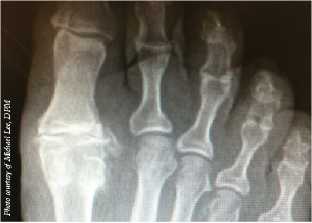

Hallux Valgus

Priya Parthasarathy, DPM, DABPM, FASPS

In a recent episode of Podiatry Today Podcasts, this thought leader dove into her experience and features from the literature on surgical intervention for this often-seen pathology in podiatric practices.